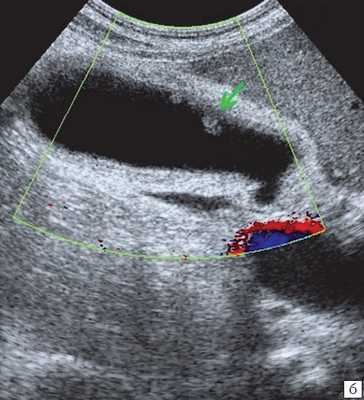

• Цветовая допплерография:

о Позволяют достоверно дифференцировать расширенные протоки (в которых отсутствуют признаки кровотока) от прилегающих сосудистых ветвей печеночной артерии и воротной вены

(Левый) На косом трансабдоминальном УЗ срезе в печени определяется умеренное расширение общего желчного протока и ответвляющихся внутрипеченочных протоков; эти изменения вызваны обструкцией протоков опухолью головки поджелудочной железы (не показана).

(Правый) При цветовой допплерографии у того же пациента отмечается отсутствие кровотока в расширенных тубулярных структурах, что указывает на то, что это и в самом деле расширенные желчные протоки. Следует выполнять цветовую допплерографию в повседневной практике для подтверждения дилатации желчных протоков.